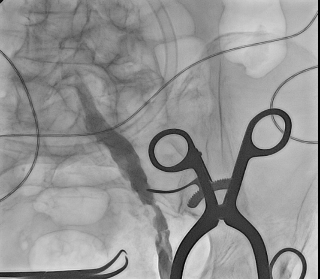

В отделении ССХ клиники ЦЭЛТ выполнена ангиография нижних конечностей

Обследование в отделении сердечно сосудистой хирургии подтвердило сложное, многоуровневое поражение артерий левой нижней конечности: аневризма наружной подвздошной и общей бедренной артерий, закупорки и сужения были обнаружены на всем протяжении – от подвздошных артерий в малом тазу до мелких сосудов голени. Кровоток до стопы доходил в малом количестве, через обходные пути (коллатерали).

Значимый стеноз общей подвздошной артерии, аневризматически расширенная наружная подвздошная артерия |

Аневризматичски расширенная общая бедренная артерия, окклюзия поверхностной и глубокой бедренной артерий |